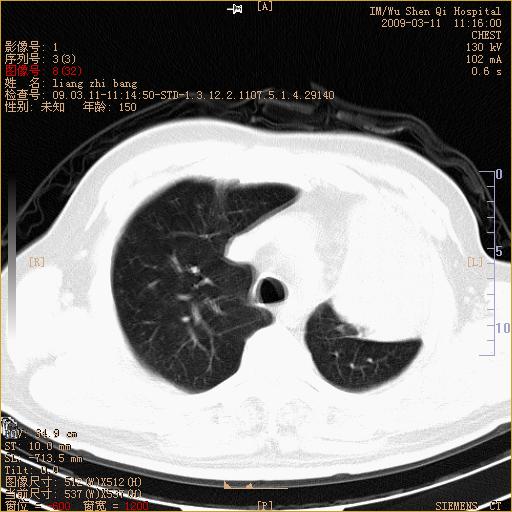

标题: CT18604:男,60岁,咳嗽一月余 [打印本页]

标题: CT18604:男,60岁,咳嗽一月余

1)考虑左肺上叶中央型肺癌并左肺上叶肺不张;建议必要时行纤支镜检查进一步明确诊断。2)左侧胸腔积液。

肺门肿块、支气管开口闭塞伴肺不张及胸水!典型的中心型肺癌变现!

1、左肺上叶中央型肺癌并上叶阻塞性肺不张。

2、左侧胸腔少量积液,右侧胸膜轻度增厚。

左肺们肿块并左肺上叶不张。考虑左肺中心性肺癌并左肺上叶不张及左侧胸腔积液